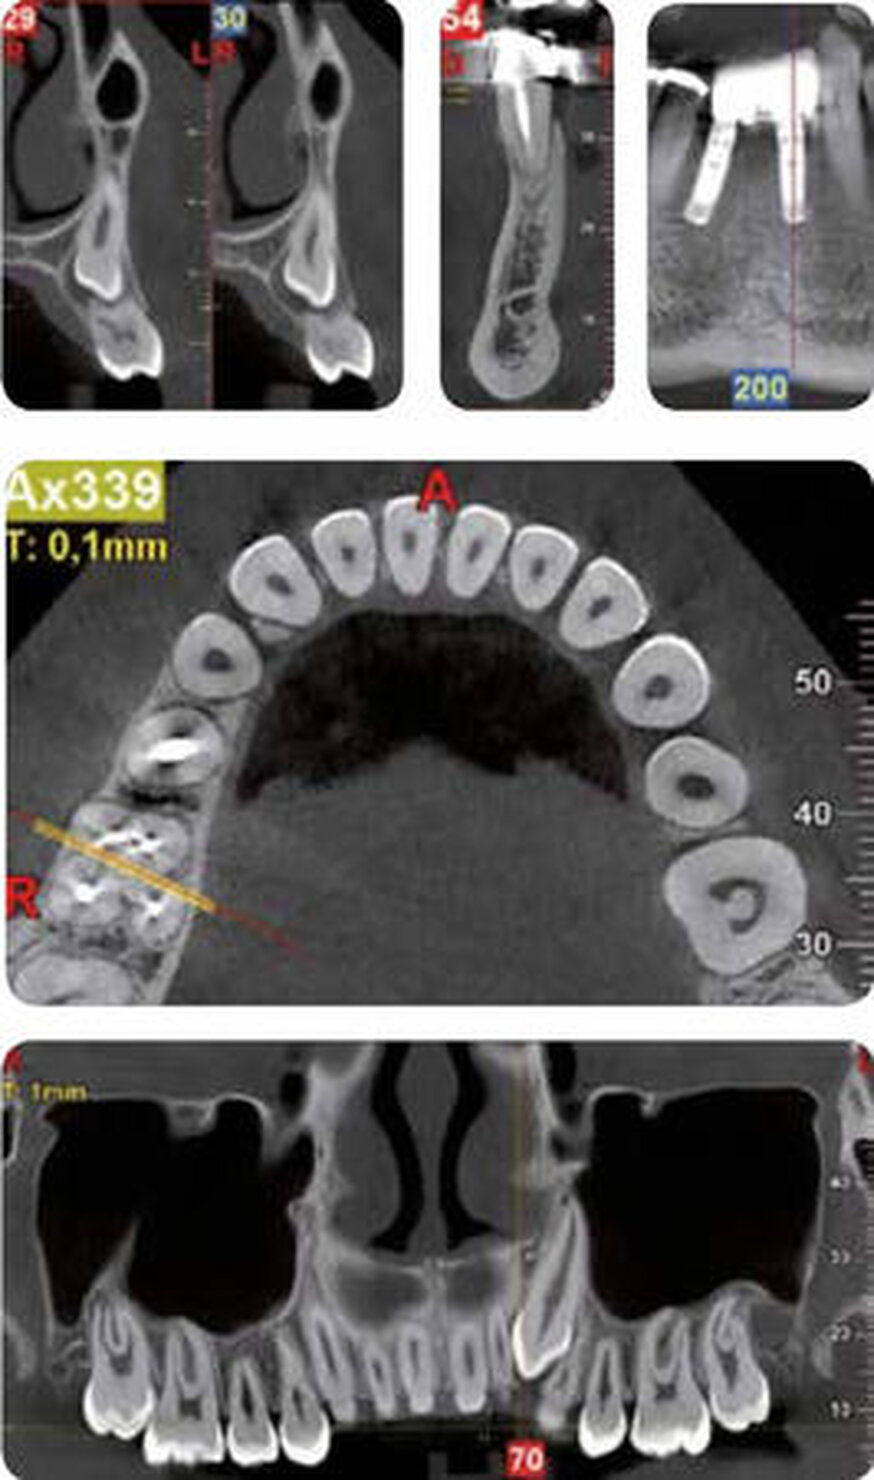

Endodonzia-Periodonzia

Lo specialista che si occupa di endodonzia e periodonzia, per eseguire procedure come il trattamento di un dente fratturato, la terapia del canale mandibolare e la cura del tessuto adiacente al dente, necessita di immagini che gli permettano di identificare ogni particolare della zona trattata, determinare l’esatta patologia e pianificare accuratamente un trattamento efficace.

Ortodonzia

Per eseguire dei trattamenti ortodontici, per fini estetici o per la cura di patologie più gravi, la radiologia a fascio conico (Cone Beam) basandosi su acquisizioni tridimensionali, produce diversi tipi di immagini, tra cui panoramiche, teleradiografie e immagini 3D. L’immagine 3D fornisce una rappresentazione esauriente dell’area scansionata, permettendo inoltre di modificare l’angolazione della visuale e di regolare lo spessore delle immagini ricostruite.